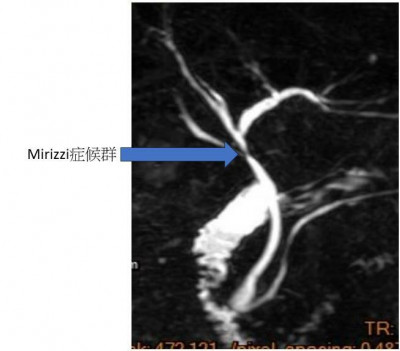

64歲謝姓男子因腹痛且臉色發黃,到衛生福利部豐原醫院就診,經外科主任袁天民初步診視研判為急性膽囊炎,安排核磁共振檢查發現為Mirizzi症候群(為膽結石卡在膽囊管或膽囊頸部)症候群,緊急安排3D腹腔鏡手術,住院5日後即康復出院。袁天民表示,Mirizzi症候群主要發生在膽管與膽囊的接口處,因膽囊頸部